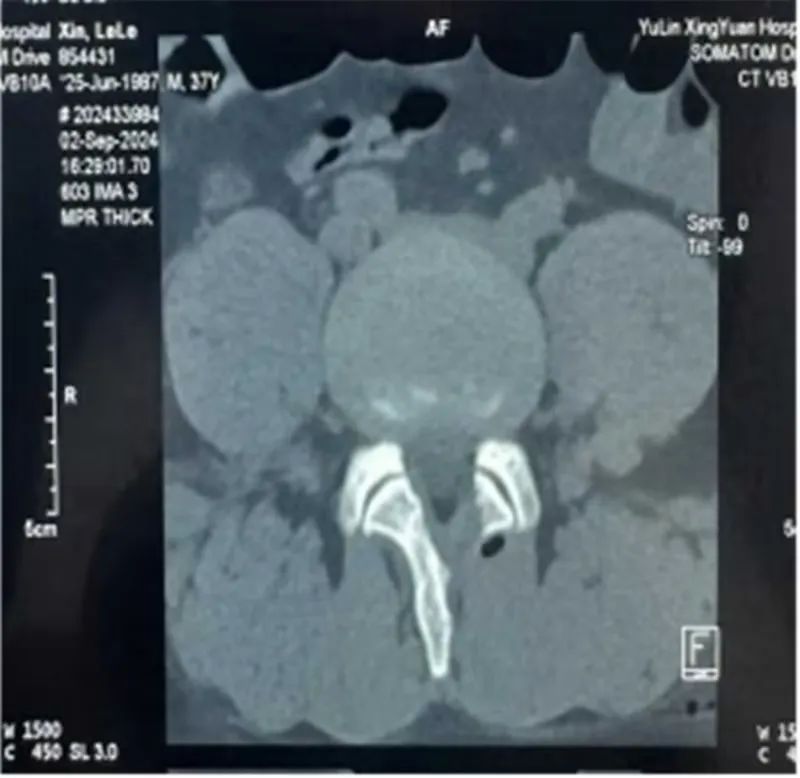

37岁的辛某某,腰臀部酸胀1年,左下肢放射性疼痛1月,曾在当地医院诊断为腰椎间盘突出症给予理疗、射频消融等治疗后症状缓解不明显,近1月来出现左下肢放射性疼痛,从臀部放射至大腿后侧、膝关节、小腿外侧,疼痛进一步加重,严重影响到患者的日常生活。不能下地活动,为寻求进一步治疗,来到市星元医院就诊。经过专科查体及影像学辅助检查,患者被诊断为腰椎间盘突出症、腰椎管狭窄症。邢永军主任医师团队综合评估患者病情,结合患者年龄、椎管狭窄程度、椎间盘退变程度、椎间隙高度等各项指标,经与患者充分沟通,开放手术创伤太大,单轴内镜受灵活性所限,不一定能够达到手术目的,“AUSS是传统脊柱手术内镜化方案,兼具开放手术和内镜手术的优势,且创伤比双通道的UBE手术更小,是目前最好的选择!,制定了“AUSS关节镜辅助单孔脊柱手术”的治疗方案。术中,医生通过可视化内镜辅助对患者狭窄的椎管进行减压、突出椎间盘进行摘除,对破裂的纤维环进行缝合,提高患者术后生活质量,术后患者恢复良好。下肢放射性疼痛完全消失。